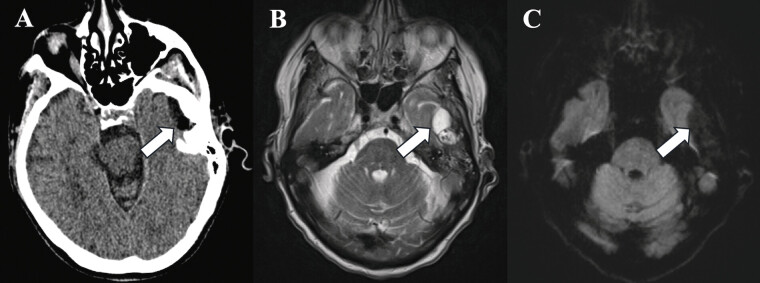

Case presentations: Three patients presenting with otalgia and TMJ tenderness were found to have intracranial cysts communicating with the TMJ. Two patients had been transferred with suspected intracranial abscesses; one presented for workup of headache and trigeminal neuralgia. All three demonstrated elevation of inflammatory markers. Two patients had TMJ aspiration, notable for leukocytosis and crystalline deposition, another had frank purulence. One patient demonstrated pneumocephalus within the cyst on imaging. The intracranial cysts ranged from 1.2 to 3.3 cm in maximum diameter, with their bony defects ranging from <1 to 4 mm. Two patients underwent craniotomy, cyst resection, and repair of the middle fossa defect, while the third opted for observation. Pathology of the white gelatinous fluid within the two resected growths demonstrated benign cysts.